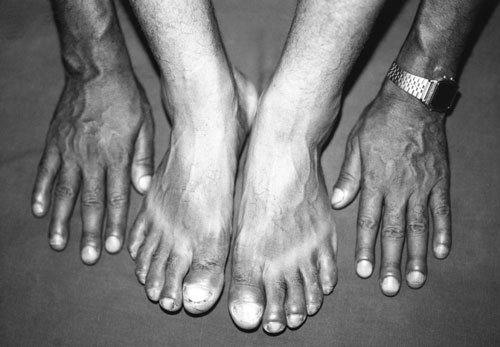

In Nepal, a 28-year-old security guard presented with a seven-year history of peripheral joint pain and clubbing of the fingers and toes (Box, Figure A). He had first noted swelling of his wrists and metacarpophalangeal joints at the age of 16 years, and later his ankles and knees were also affected. The joints were intermittently painful, particularly after he consumed alcohol. The clubbing had developed insidiously. He reported that his brother had similar swelling of the fingers and toes. He also reported excessive perspiration, erectile dysfunction and diminished libido.